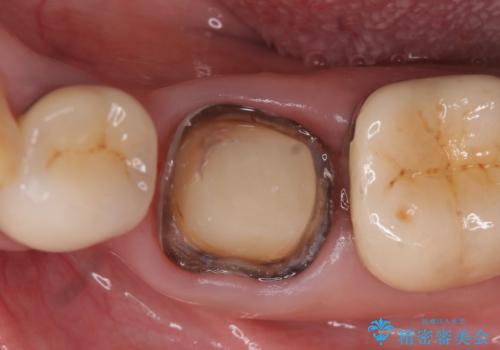

検査の結果左下6に根尖病変を認めたため、再根管治療を行いました。

その後症状の消失を確認し、オールセラミッククラウンによる補綴を行いました。

今回用いたオールセラミッククラウンはジルコニアフレームという白い素材の上にセラミックを盛っているため、審美性が非常に高いのが特徴です。

また、ジルコニアは人工ダイヤモンドの材料にも使われているほど高い強度を持っており、そのためオールセラミッククラウンは審美性だけでなく、奥歯やブリッジの補綴も可能とするクラウンです。